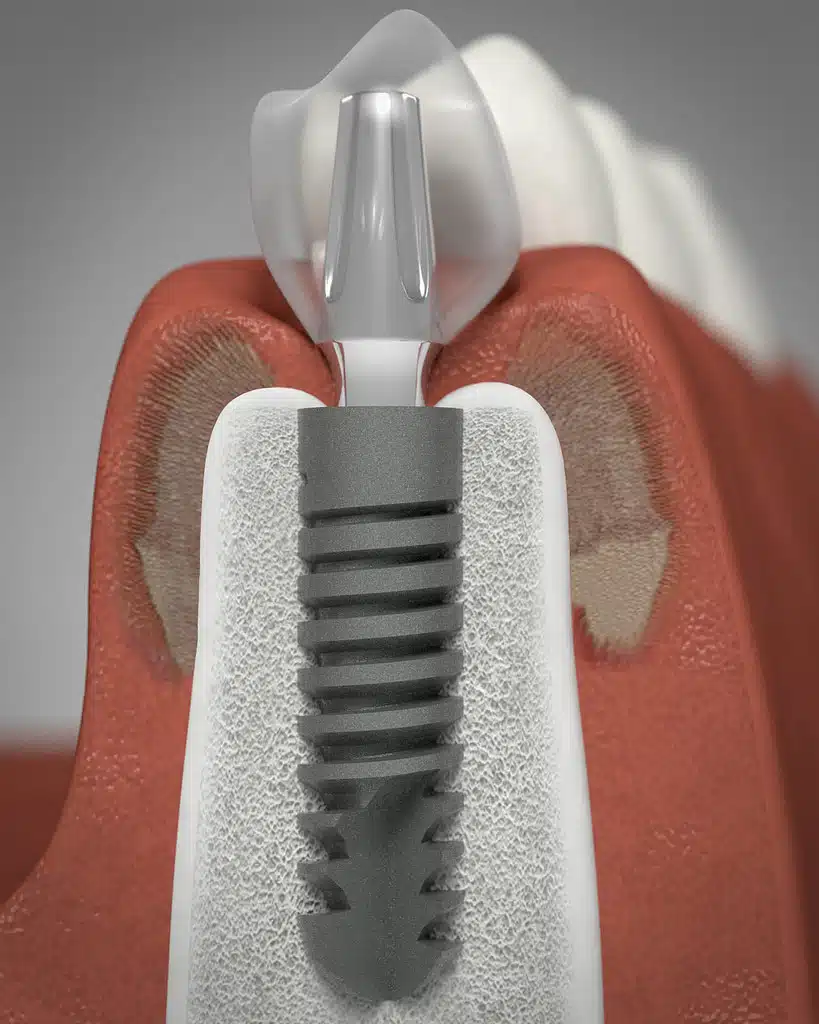

Dental implants are the very best way to replace missing teeth. Always performed by a specially trained implantologist or periodontist, this treatment is carefully planned using 3D x-ray imaging. Actually, the dental implant procedure is not as complex as most people think and is not a painful procedure at all. An implant can be placed in about 30 minutes or less.

A dental implant is a special screw which replaces the root of a missing tooth. Once placed, this normally needs three months to settle and heal into the jaw bone before the final stage is completed.